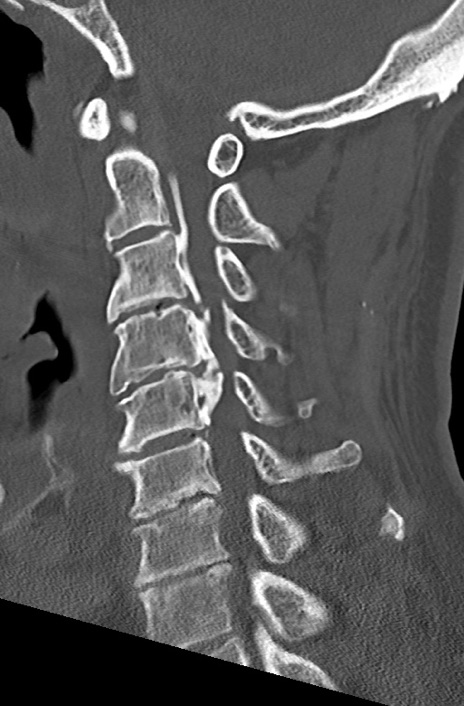

【整形】TIPS症例7 頚椎CT(矢状断像)

頚椎CT

矢状断像と横断像